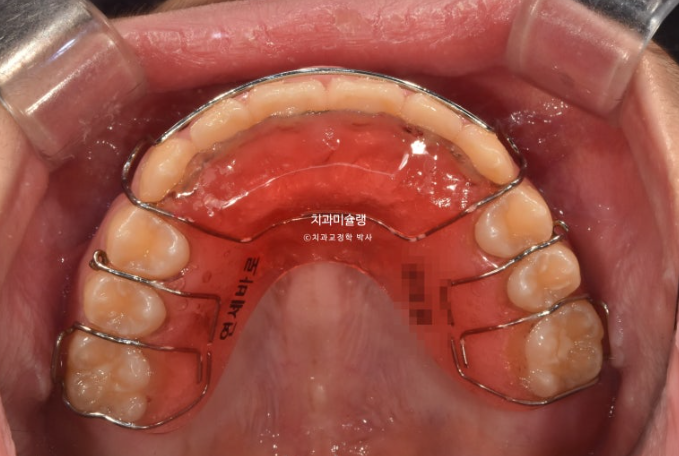

치료결과가 성인교정치료 결과에 준하는 만큼 유지장치도 성인과 동일하게 들어갑니다.

단 과개교합 재발 방지를 위해서 유지장치에 ABP교합판을 추가하는 것이 안전합니다.